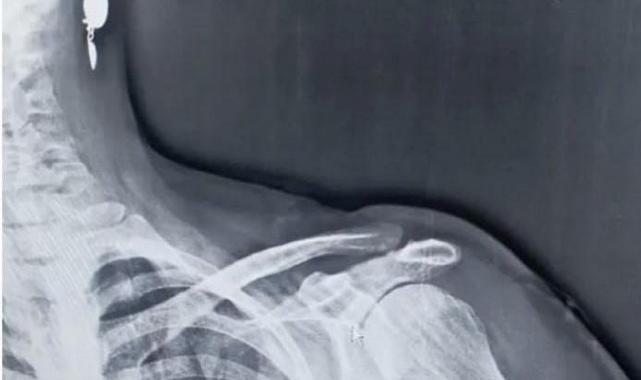

Trabzon’un Tonya ilçesinin Karğaç Mahallesi yakınlarındaki Hırsafa Yaylası’nda 2022 yılının Kasım ayında ot biçen Asiye İnce (59), sol omuz bölgesinden giren yorgun mermi ile yaralandı. Hastanede tedavi altına alınan İnce mermi çekirdeği ameliyatla çıkartılması sonucu sağlığına kavuştu.